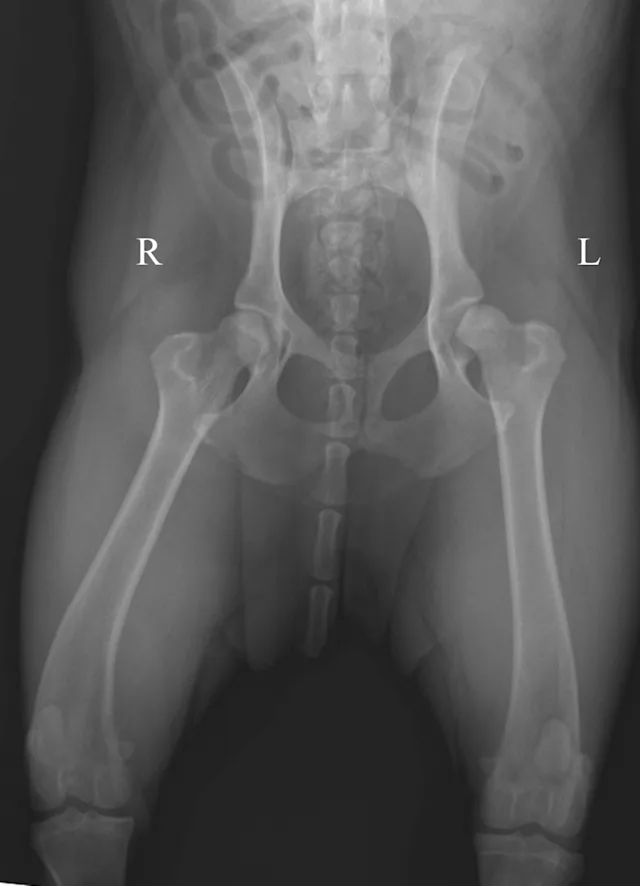

The ventrodorsal radiograph with the legs lying in a neutral to flexed position is often called the "frog-legged" position. This view is particularly useful in cases of pelvic trauma because minimal stress is placed on the pelvis and coxofemoral joints. The dog is placed in dorsal recumbency in a foam positioning trough and the limbs are not held. It is still important to maintain symmetry of the pelvis and limbs. Figure 5A demonstrates a dog positioned for this view. Figure 5B shows an example of this positioning in a cat with bilateral capital physeal fractures (white arrows).